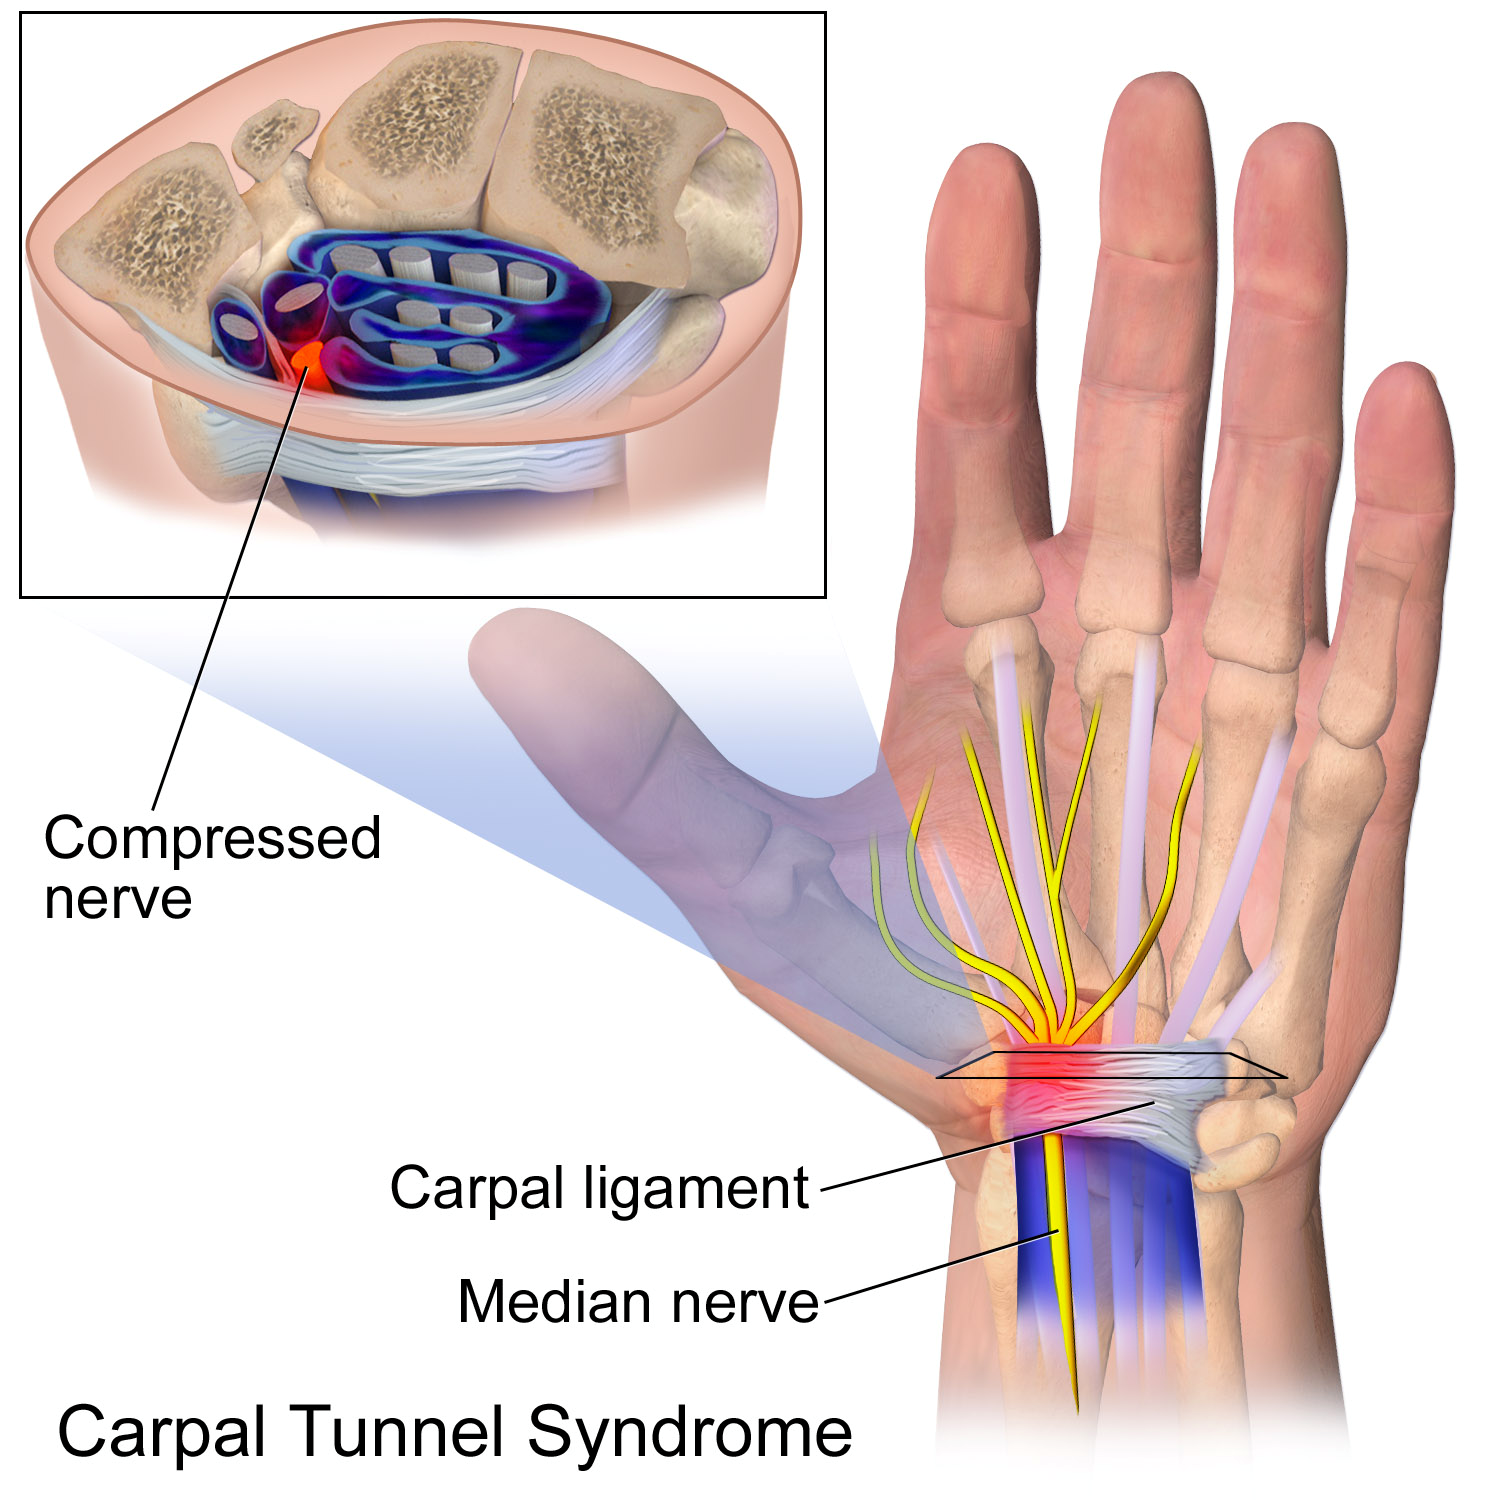

To fully understand Carpal Tunnel Syndrome, let us first take a look at the photo on the right.

The tunnel located at the center of the wrist (colored in purple-black) is formed between tendons, ligaments and bones from the arm to the hands. It serves as a ‘passageway’ of the nerves, hence, called the ‘carpal tunnel’.

The median nerve (yellow-colored structure) passes through the tunnel and serves as the ‘communicator’, like an electrical wiring network, providing sensations to the thumb and nearby fingers (see photo about median nerve’s area of sensation). This nerve also controls the muscles in the palm, allowing them to move.